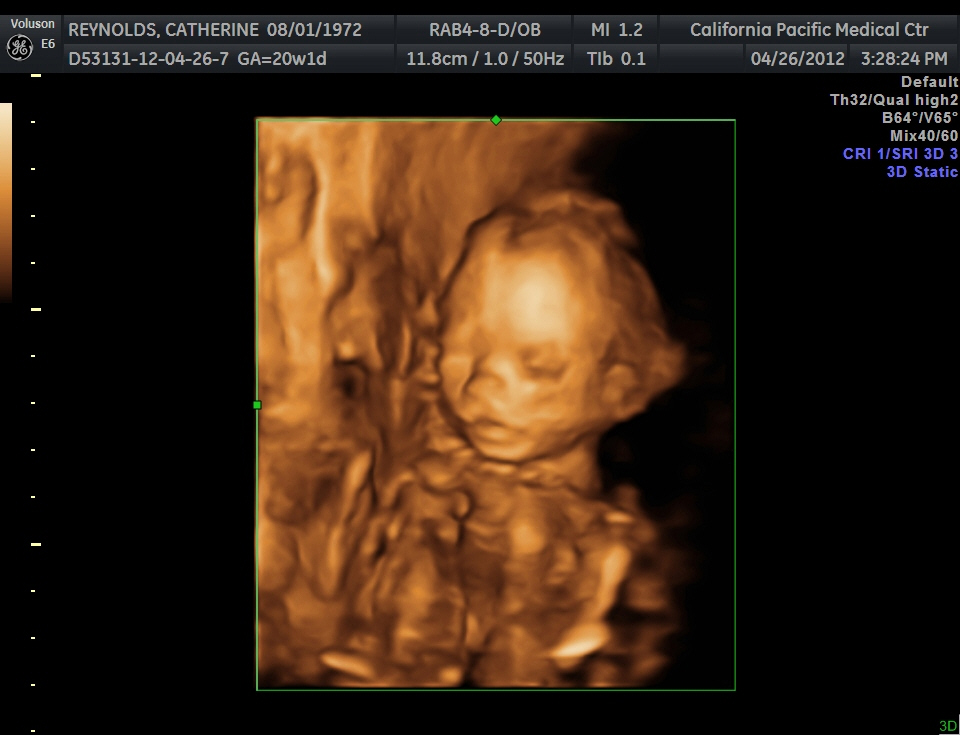

This week we had another ultrasound (sonogram). It's an opportunity to find out whether the tiny human is male or female. Joakim and I had been wanting to keep the sex a surprise, but in the cab ride to the hospital we discussed letting the physician find out and give us the news in an envelope so we could perhaps share with family later on. Unfortunately baby was in on our initial plan and decided to keep his/ her legs well and truly closed as he was happily sleeping, so we couldn't get a peek. So a surprise it will be. The good news is that all looked good on the sonogram and we even were able to get a 3D image where you can make out his/ her face. Looks like the wee bean has Joakim's forehead and my nose :-)